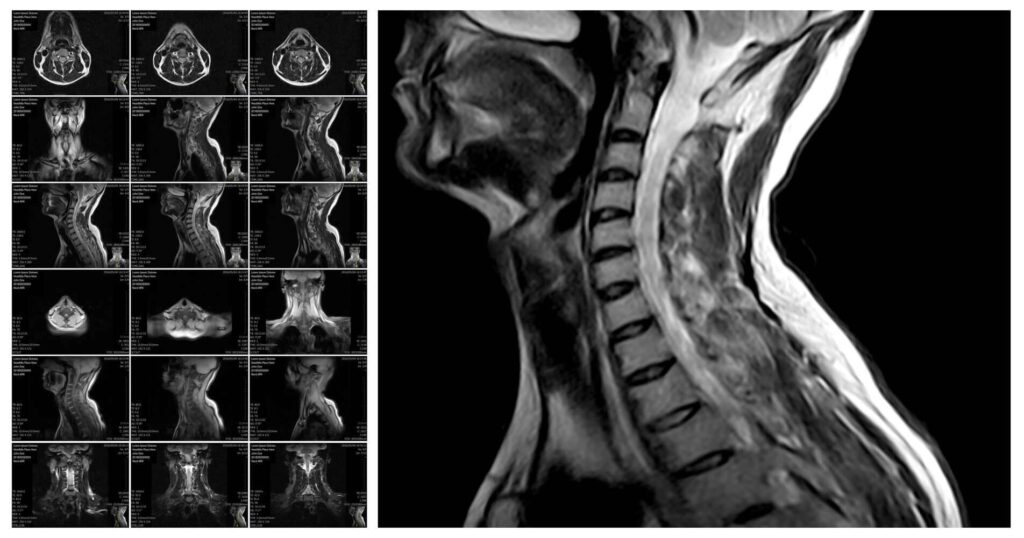

In der MRT werden mit einem starken Magnetfeld durch die elektromagnetische Anregung und Relaxation von Wasserprotonen im Gewebe Bilder erzeugt. So kann das Innere des menschlichen Körpers sehr detailliert und – im Gegensatz zur CT – ganz ohne Röntgenstrahlung abgebildet werden.

Dafür wird unser Körper Schicht für Schicht gescannt, sodass zunächst zahlreiche zweidimensionale Schnittbilder in hoher Auflösung angefertigt werden. Diese können anschließend am Computer übereinandergelegt werden, wodurch ein dreidimensionales Bild entsteht.

Dabei besticht die MRT durch einen hohen Weichteilkontrast – insbesondere Bindegewebe inklusive Nerven und Gefäßen, Muskeln und Fettgewebe lassen sich optimal beurteilen. So lassen sich sowohl entzündliche Prozesse als auch tumoröse Veränderungen der Halsweichteile, der Speicheldrüsen, des Rachens und des Kehlkopfes hervorragend darstellen und sicher befunden.

Auch die Halswirbelsäule und Teile des Rückenmarks sind auf einer MRT des Halses in der Regel dargestellt, sodass auch hier mögliche Pathologien diagnostiziert oder ausgeschlossen werden können.